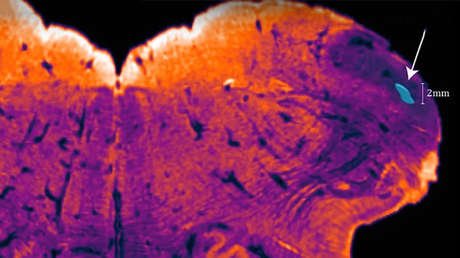

Los científicos han denominado la zona como "núcleo endo-restiforme", porque se encuentra dentro (endo) del pedúnculo cerebeloso inferior (también llamado cuerpo restiforme). El área participa en la recepción de información sensorialy motora para el mantenimiento del equilibrio y los movimientos del cuerpo.

Los neurocientíficos han dado con la estructura cerebral mientras usaban una técnica de tinción cerebral relativamente nueva para aclarar imágenes de los tejidos cerebrales en plena tarea de elaboración de su último atlas de neuroanatomía. Esta técnica ayuda a diferenciar los grupos neuronales por su función, lo que contrasta con la forma tradicional de separarlos según el aspecto de las células.